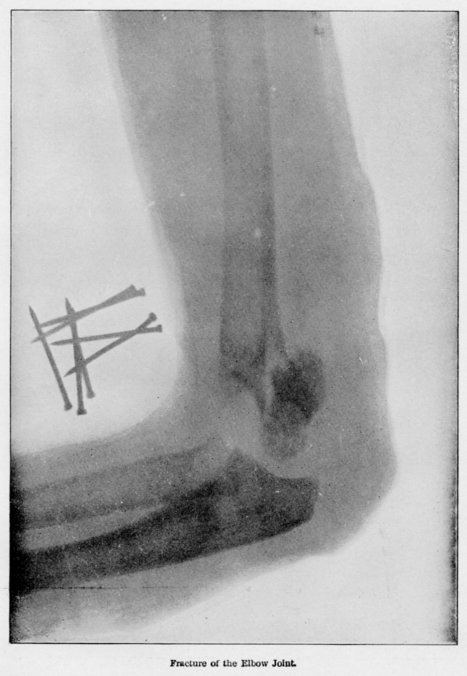

The discovery and application of the X-ray has proved of immense value to medicine and surgery. By its means the physician is enabled to carry on far-reaching diagnoses, and to ascertain with certainty the whole internal structure of the human body. Fractures, dislocations, deformities and diseases of the bones may be located, and their character and treatment decided upon. In dentistry the teeth may be photographed by means of the X-ray, even before they come to the surface, and broken fangs and hidden fillings may be located. Foreign objects in the body, as bullets, needles, calculi in the bladder, etc., may be located, and the surgery for their safe removal greatly simplified. The beating of the heart, movement of the ribs in respiration, and outline of the liver and other organs may be exhibited to the eye. It has even been suggested that the X-ray may become an agency for destroying the bacilli which produces disease in the human body. Verily the X-ray opens the field for the grandest of electrical possibilities.